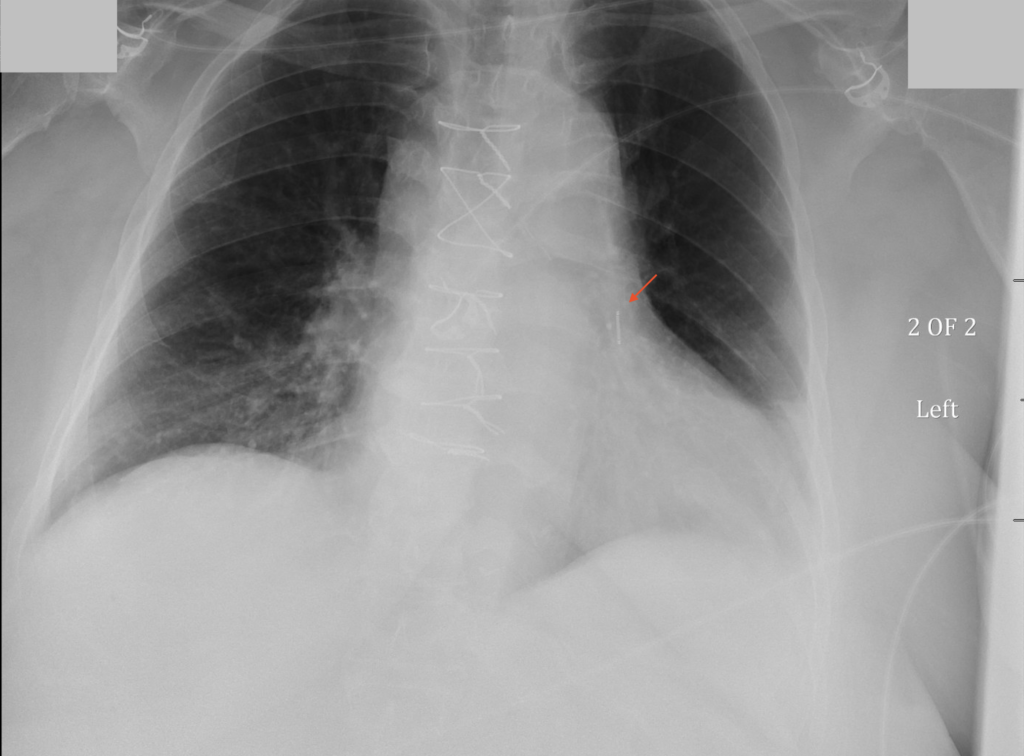

Radiographic Appearance

Note the Presence of the CardioMEMS Superimposed Over the Left Pulmonary Artery in the Following Chest X-Ray (and Inset)